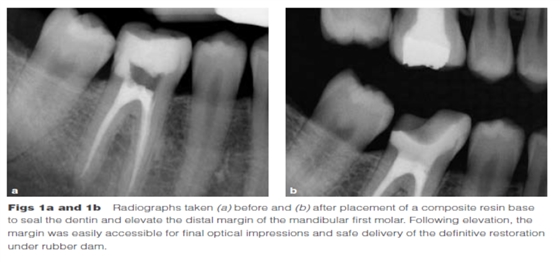

Dietschi和Spreafico在1998年提出了另一種方法,即在間接修復體的下面放置一個復合樹脂基底來取代冠向提升邊緣(圖1)。這個方法即我們所知的齦壁提升術(shù)(DMG)是在橡皮障隔離下完成的?(This procedure,…,is performed under rubber dam isolation following the placement of a matrix.)如今,DME(齦壁提升術(shù))通常與IDS(即刻牙本質(zhì)封閉術(shù))聯(lián)合使用來促進間接粘接修復體的粘接和齦邊緣的封閉。此外,邊緣的齦上提升,粘接復合樹脂基底被用于封閉牙本質(zhì)、加強潛在牙尖?(reinforce undermined cusps),充填倒凹(fill undercuts),以及為嵌體/高嵌體修復提供必要的幾何形態(tài)。

DME是用一個改良彎曲的成型片接堆放復合樹脂來提升齦壁高度,使其能夠在修復過程中使用橡皮障封閉邊緣,可以在固化前適當?shù)囊瞥嘤嗟膹秃蠘渲?。DME應(yīng)該在即刻牙本質(zhì)封閉(IDS)之后,在使用橡皮障的條件下,且僅在邊緣可被改良的成型片適當隔離時直接獲得。否則,這個技術(shù)不能使用。在最終取印前,需要拍攝咬合翼片來評估復合樹脂在齦邊緣區(qū)域的密合度(有無懸突或缺陷)。同樣需要仔細隨訪來評估軟組織的健康和是否需要外科手術(shù)干預。只要可能,在牙髓治療前就應(yīng)通過DME術(shù)制造假壁,使根管治療更完善(圖2、3)。圖4展示了一個典型DME術(shù)的適應(yīng)癥。